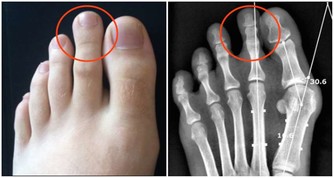

一說起尿毒症可能大家現在都不太陌生,尿毒症是指身體不能通過腎臟產生尿液,把身體代謝所產生的廢物,還有多餘的水分排出體外而引起的毒害,尿毒症是腎功能下降

為何“尿毒症”越來越多?

根據資料統計顯示,我國尿毒症患者從2011年的27.6萬人增長到2006年的50.1萬元,年復合增長率達到12.66%,

而且逐漸呈現年輕化的趨勢,根據相關統計數據的顯示,大概在每10個尿